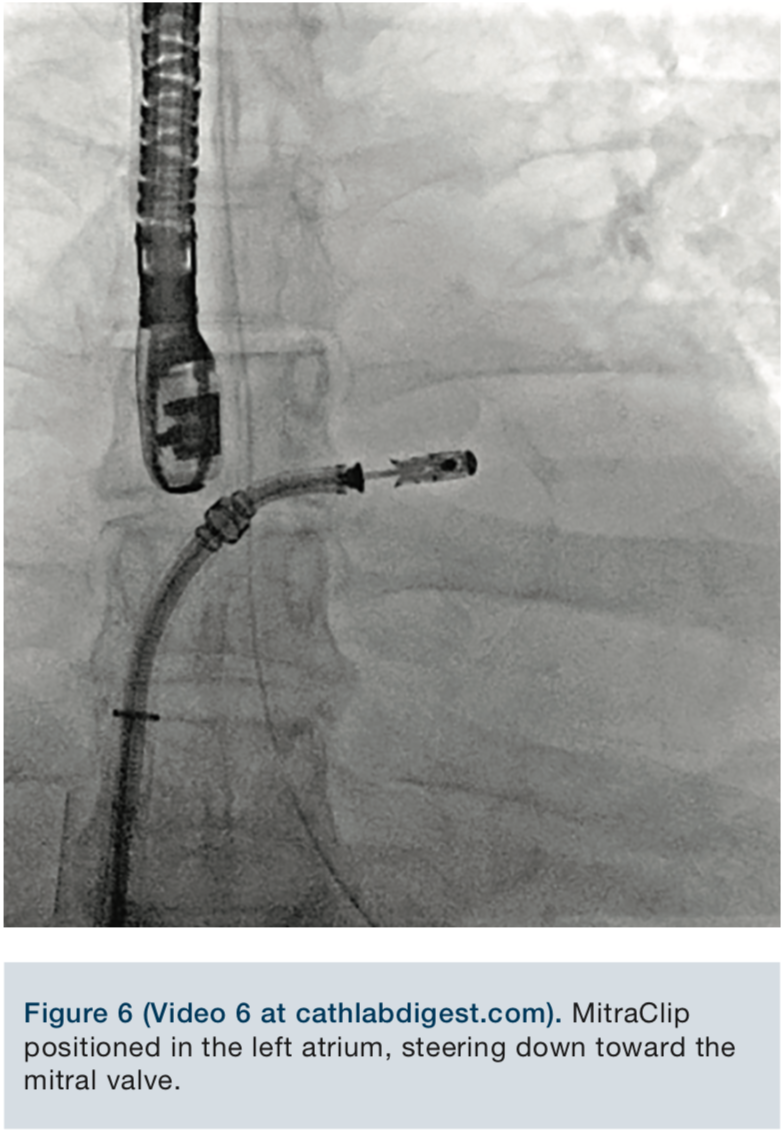

Video 6. MitraClip positioned in the left atrium, steering down toward the mitral valve.

The MitraClip delivery system was then advanced into the left atrium, and the delivery system was placed into a suitable position over the targeted area, under fluoroscopic and echocardiographic guidance. The clip was advanced into the left ventricle and retracted, trapping the leaflets. The mitral regurgitation was evaluated with the clip partially closed and found to be significantly reduced. The regurgitation was essentially eliminated, and the clip was fully closed.